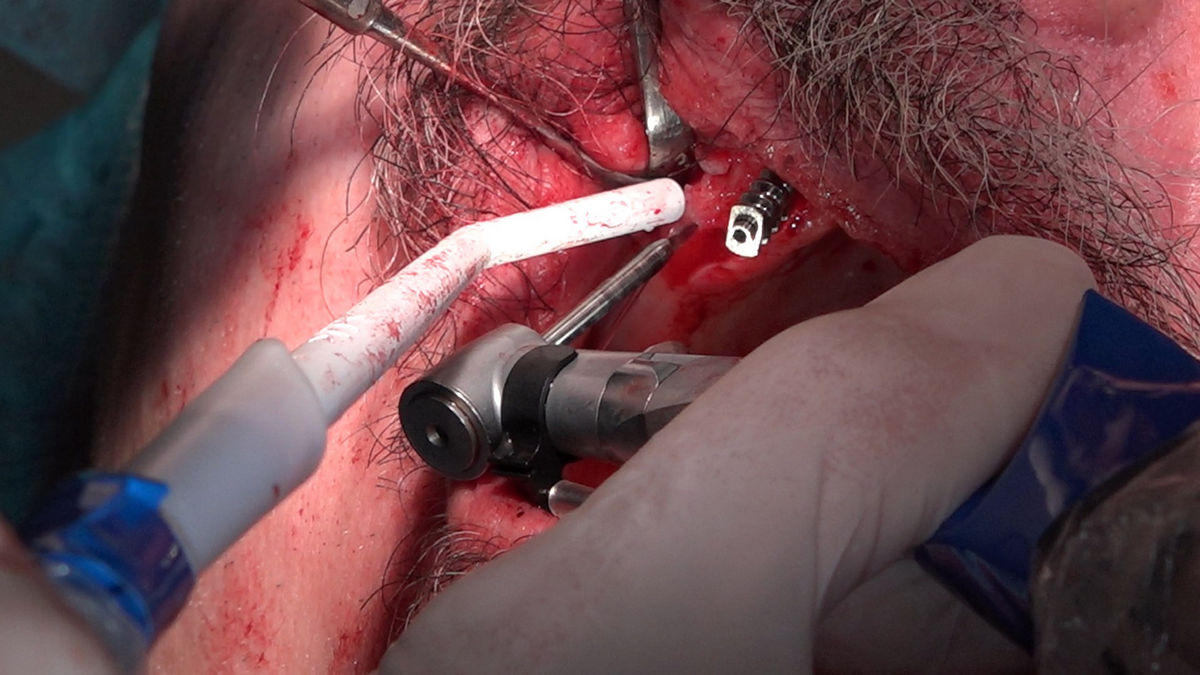

Chirurgia implantologiczna to temat wiodący 5 Sesji X Sezonu Practiculum Implantologii, która się odbyła 23-24 października 2020 roku. Bierze w nim udział 16 adeptów implantologii stomatologicznej. Zabiegi z udziałem Pacjentów jak zwykle poprzedziło omówienie i planowanie, tym bardziej, że zgodnie z planem wykonana została implantacja z wykorzystaniem szablonu chirurgicznego, który przygotowało laboratorium dentystyczne Wiligała Lab. Kursanci wykonywali szereg zabiegów implantologicznych i chirurgicznych oraz regeneracyjnych z zastosowaniem PRF, w tym sinus lift. Przeprowadzali je pod kierunkiem Lidera Umiejętności Implantologicznych dr n.med. Violetty Szycik, która wysoko oceniła wykonanie zabiegów.